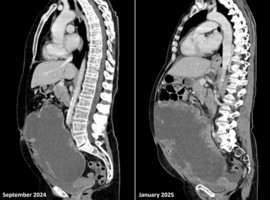

The Yule Log: Intrapulmonary Wooden Foreign Body Retained for Four Decades